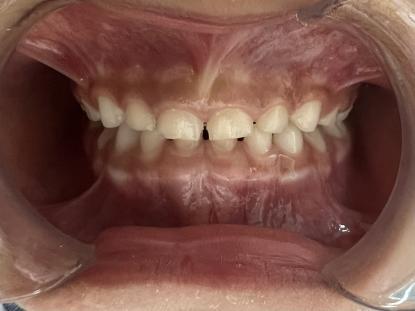

金晓月医生案例分享

案例一:

治疗前

治疗后